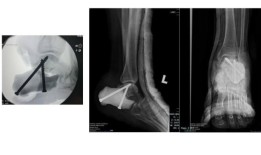

哥打京那巴卢:马来西亚首个3D打印模塑跟骨(跟骨 替代物,由伊丽莎白女王医院的肿瘤学家团队在一名年轻...